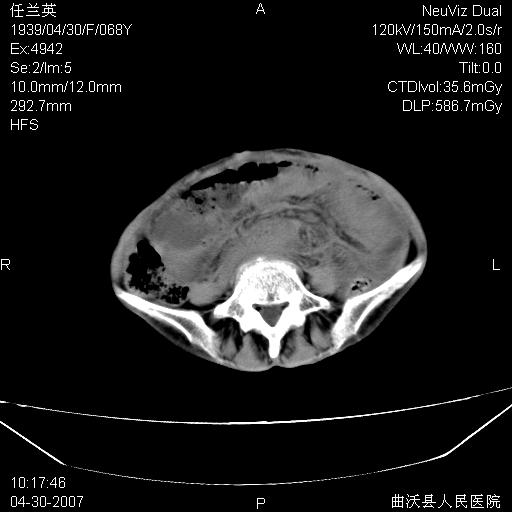

患者,女,68岁,感觉腹部憋涨发硬数天,查b超发现左盆腔有囊性肿物和少量腹水,行ct检查

1.考虑卵巢肿瘤并腹腔广泛性转移可能性大;

2.腹盆腔少量积液。

支持左侧卵巢恶性肿瘤伴网膜、腹膜广泛转移。

支持:左侧卵巢恶性肿瘤伴网膜、腹膜 腹膜后(淋巴结)广泛转移。

网膜、腹膜广泛转移考虑来源于左侧卵巢癌可能性大。不除外来源于消化系的肿瘤。

难的一见 典型 - 网膜饼  冰冻骨盆 可以当教学片了